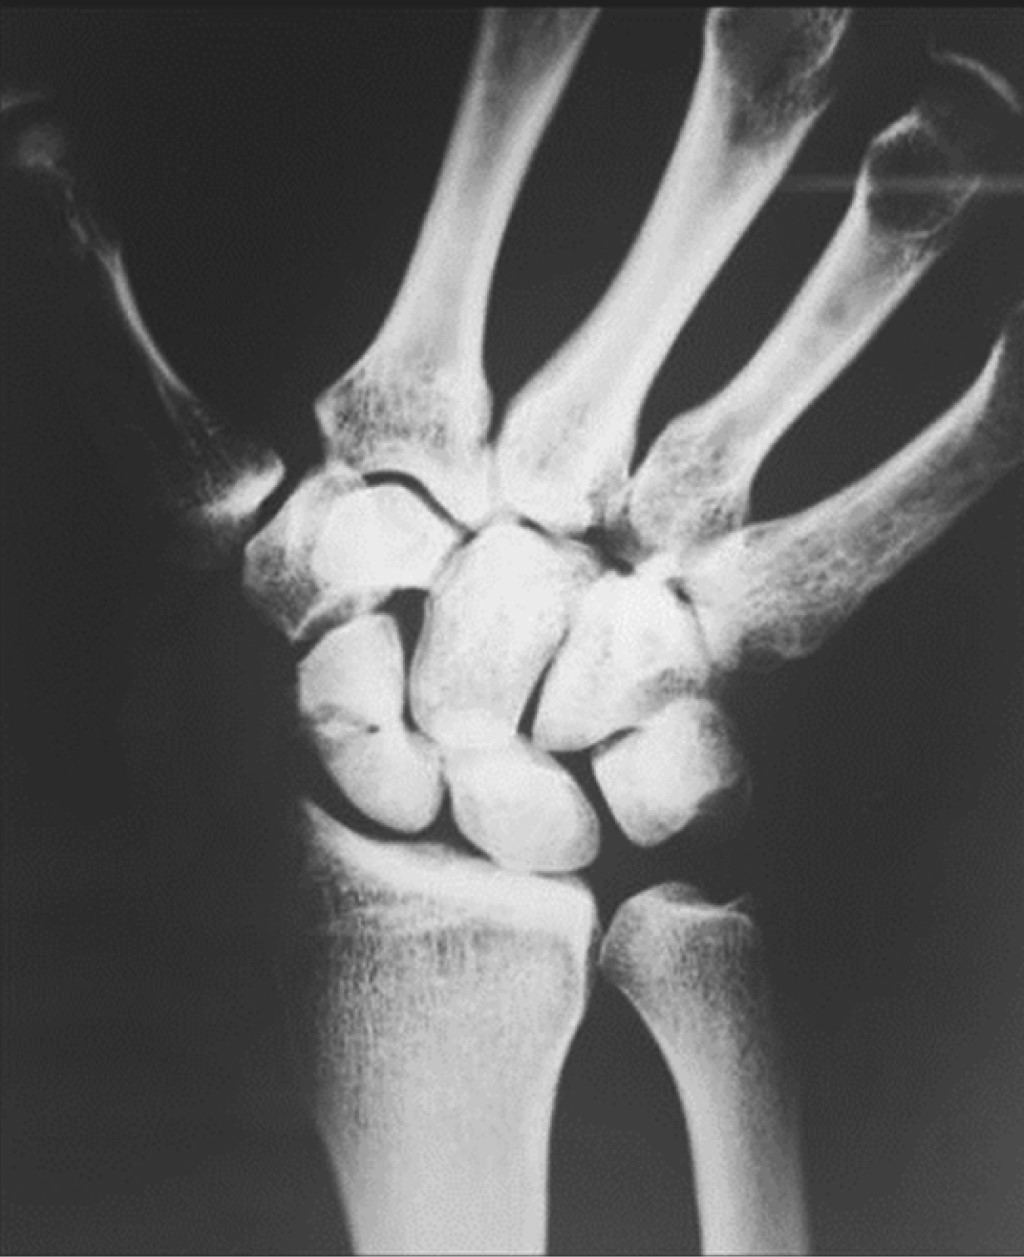

A 28-year-old right-handed male, with no comorbidities, sustained a wrist injury when he fell from his own height and landed with an outstretched right hand. He evolved with swelling, limitation of movement, and tenderness on palpation in his anatomical snuff box. He was initially assessed in another institution where through plain radiographs the diagnosis of scaphoid fracture was made. It was classified as a Herbert and Fischer type B2 (complete displaced scaphoid waist fracture) (Figure 1). Consequently, he was immobilized with a below-elbow cast without the inclusion of the proximal phalanx of the thumb. After three weeks, the patient removed his cast and decided to abandon the treatment and medical follow-up. At seven months he consulted again for pain. Once more, posteroanterior, lateral, and scaphoid (30° wrist extension, 20° ulnar deviation) plain radiographs of the wrist were requested (Figure 2). The fracture exhibited absence of consolidation. Due to the evolution time (more than six months from the initial trauma), a scaphoid nonunion was diagnosed. A CT scan was requested to assess displacement. This revealed a Herbert type D nonunion (established nonunion), with no density alteration in the scaphoid fragments and no displacement (Figure 3). According to the Slade and Geissler classification, it was a grade II nonunion, with no sclerosis, no bone cysts, and a small resorption edge. Surgical treatment was indicated, but the patient refused. Then he returned to our institution 10 months after the initial injury. He presented with pain in the anatomical snuffbox, on axial compression of the first metacarpal, and on palpation of the scaphoid tubercle. Mobility was similar to the contralateral side but painful (visual analogue scale [VAS] 7/10) (Table 1). Surgical treatment was once more indicated. The patient was then lost in follow-up and returned to control 15 months after the initial injury without having undergone any type of treatment or immobilization. He showed a spontaneous clinical improvement, a complete absence of pain (VAS 0/10) and range of motion, and grip strength similar to the healthy contralateral side (Table 1). Plain radiographs and CT scan with 3D reconstruction were requested. The new images showed scaphoid consolidation (Figures 4 and 5).

Figure 2